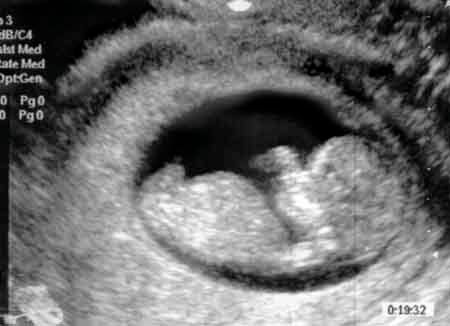

Малыш как будто лежит загорает ?одна ручка под головой, вторая у рта

???та ну да))) мы с гинекологом тоже с этого смеялись))) как на курорте прям)